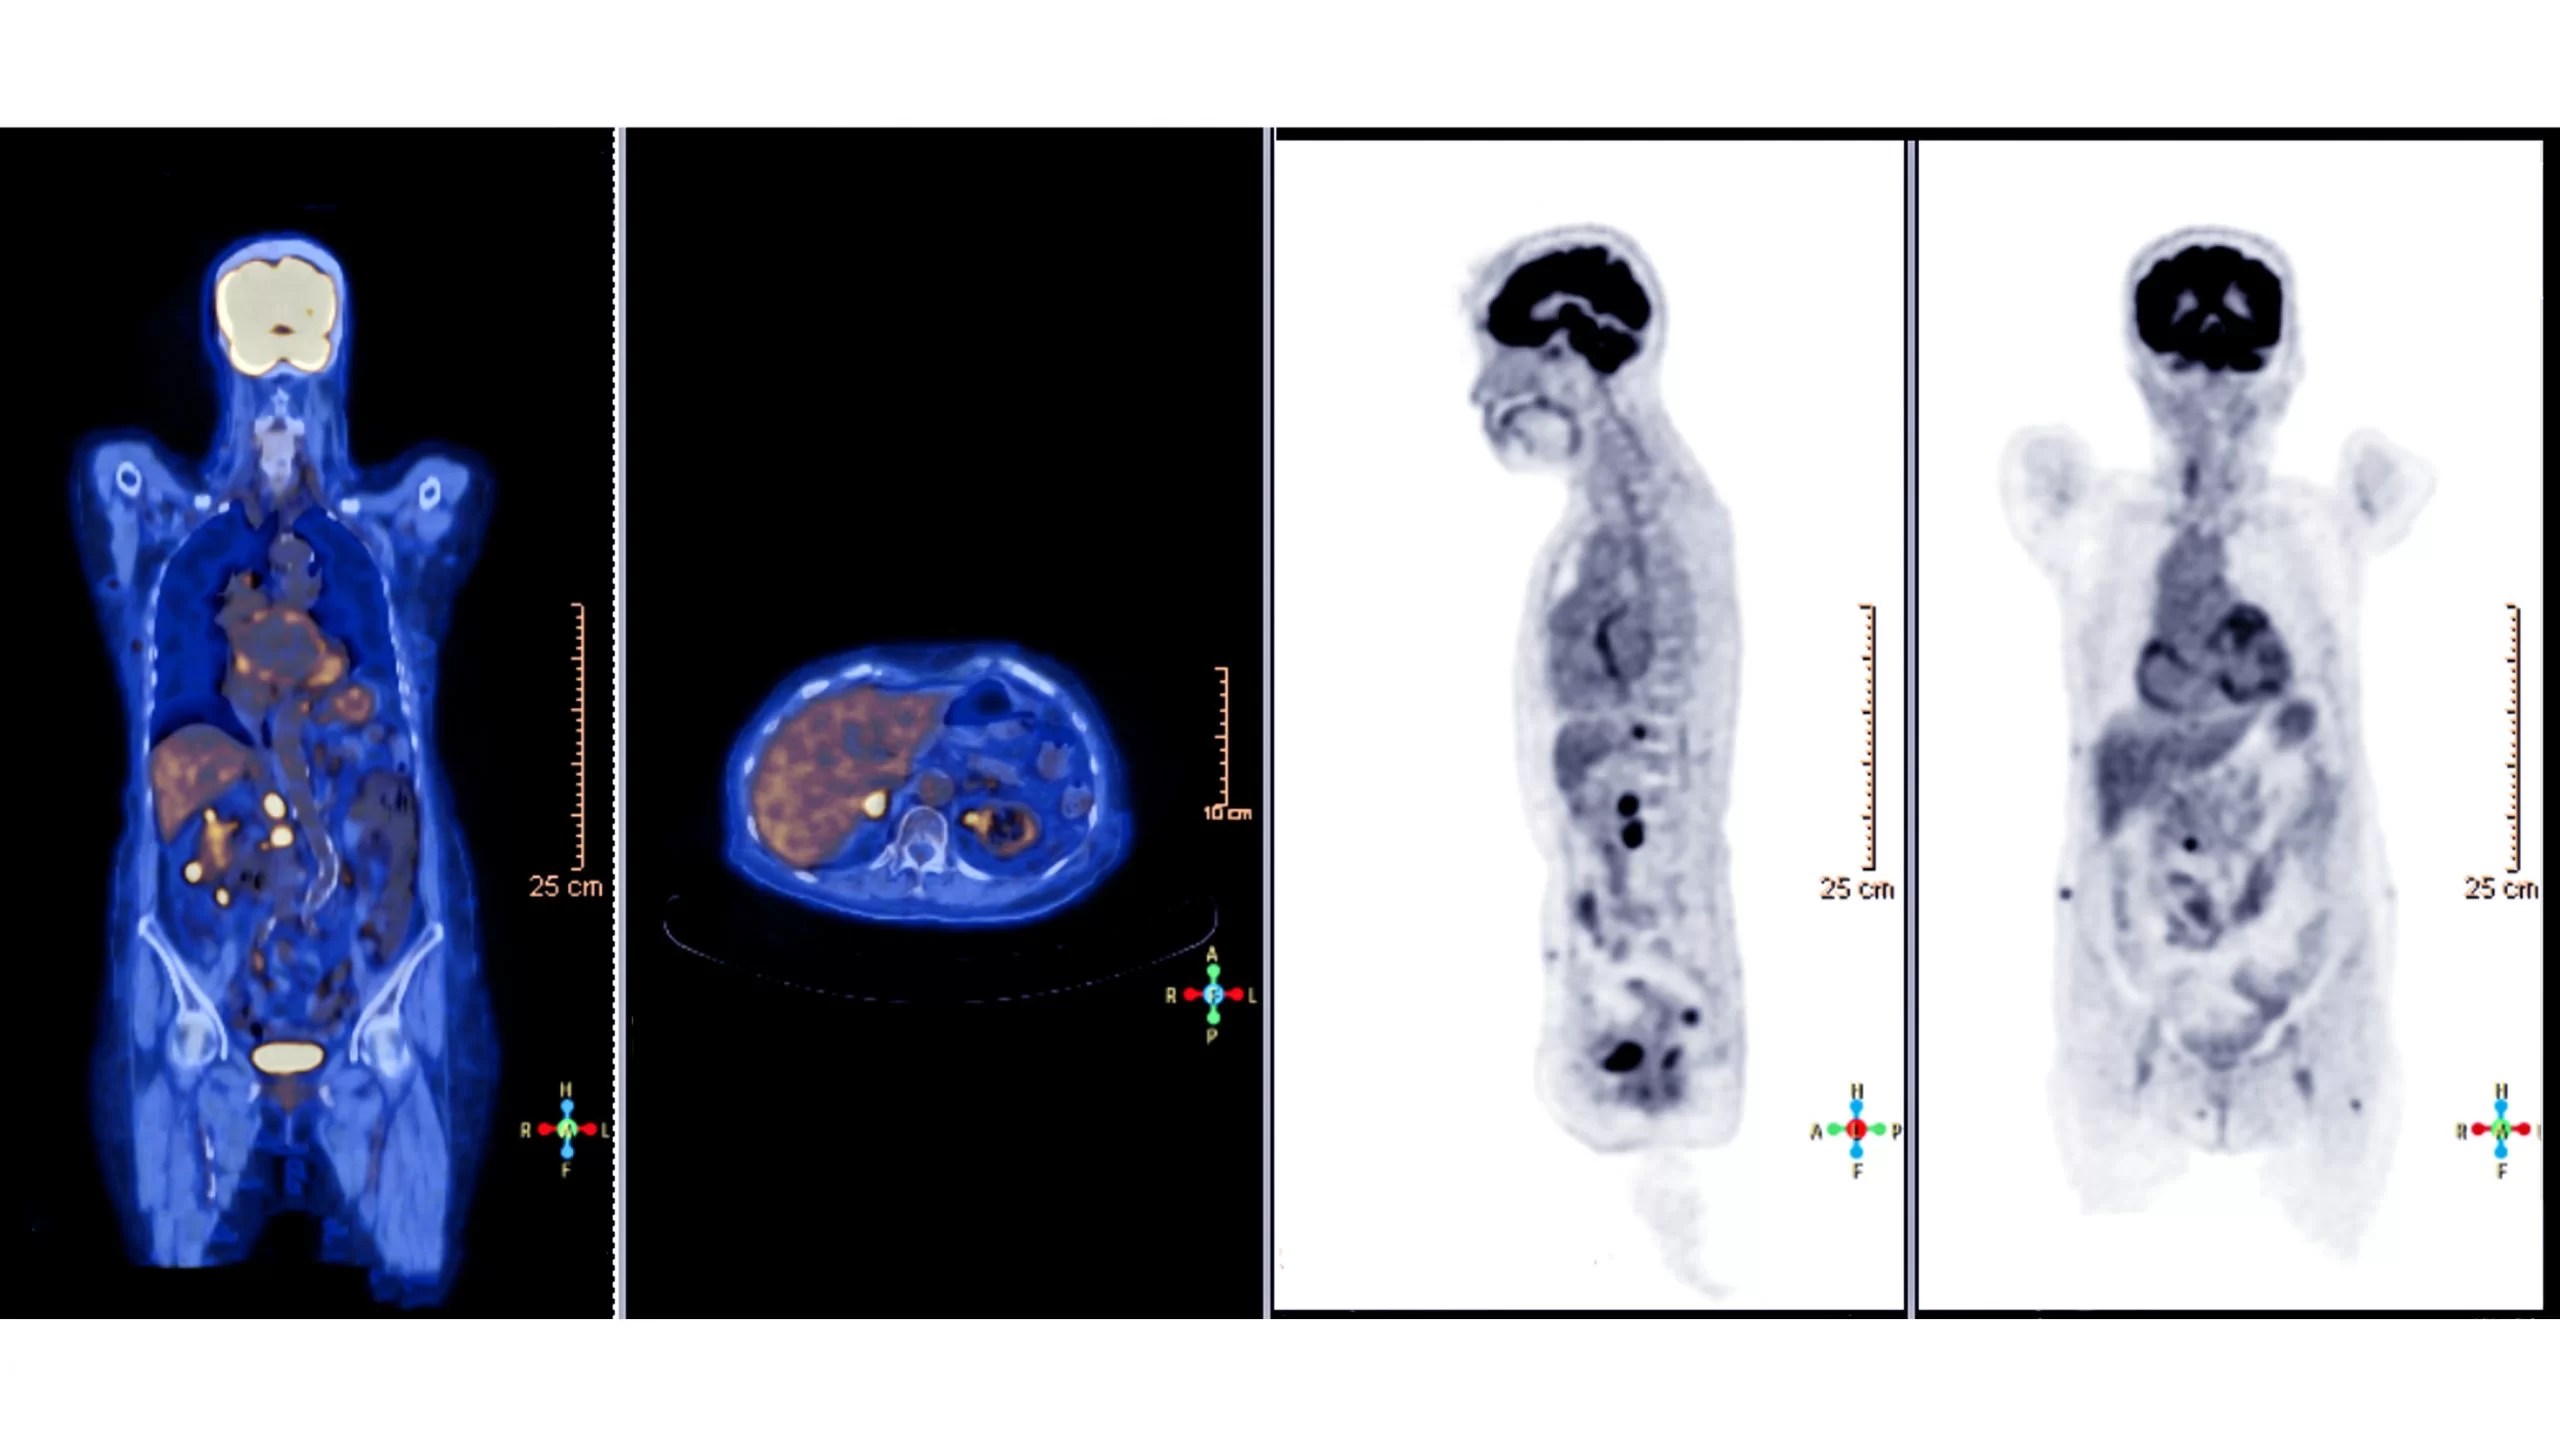

From www.researchgate.net

PET scans before and after widefield radiation therapy. Download What To Do Before Getting A Pet Scan Pet scan preparation begins a few days before the scan. To make sure your doctor gets the information he or she needs, it's important to prepare for your pet scan. As a general rule, you would avoid high glycemic index (gi) foods like bread, dairy, pasta, and juices that raise your blood sugar. Follow your pet scan prep for best. What To Do Before Getting A Pet Scan.